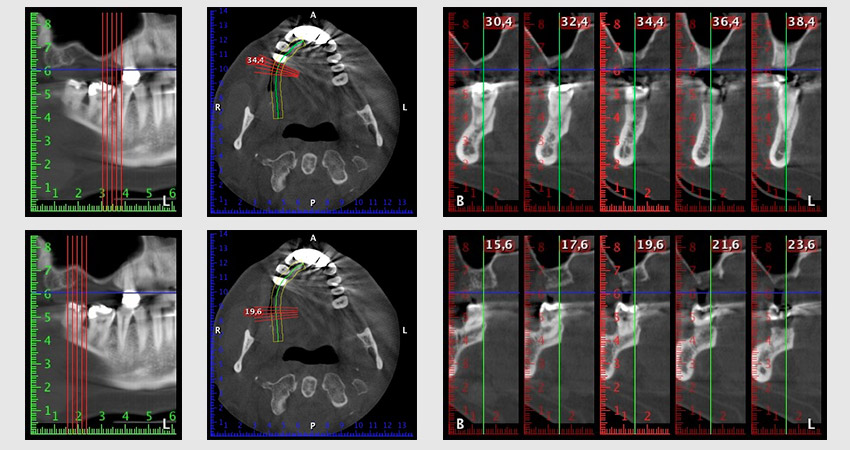

Al fine di pianificare e minimizzare i rischi, circa sei mesi dopo l'estrazione dei denti 16 e 14 viene effettuata una tomografia digitale volumetrica (DVT, Planmeca), la quale conferma chiaramente la mancata rigenerazione ossea nel volume desiderato (da fig. 2 a 7).

È necessario un rialzo del pavimento sinusale nelle regioni 16 e 14 per garantire una solida ricostruzione basata su almeno due impianti. Si auspica un accrescimento osseo su scala relativamente ampia a causa del volume osseo residuo estremamente ridotto in questo caso. Le principali procedure di accrescimento osseo sono invasive e incrementano il tasso di morbilità dei pazienti, oltre a essere costose in termini di tempo e denaro. Prevedere l'esito del trattamento diventa più difficile e il rischio di insuccesso aumenta. Il dentista informa la paziente e le propone una soluzione asportabile, fermamente rifiutata.

Per ridurre l'accrescimento nella regione 14, con il consenso della paziente si opta per il posizionamento e l'inclinazione dell'impianto 16 in direzione dorso-craniale (fig. 8).